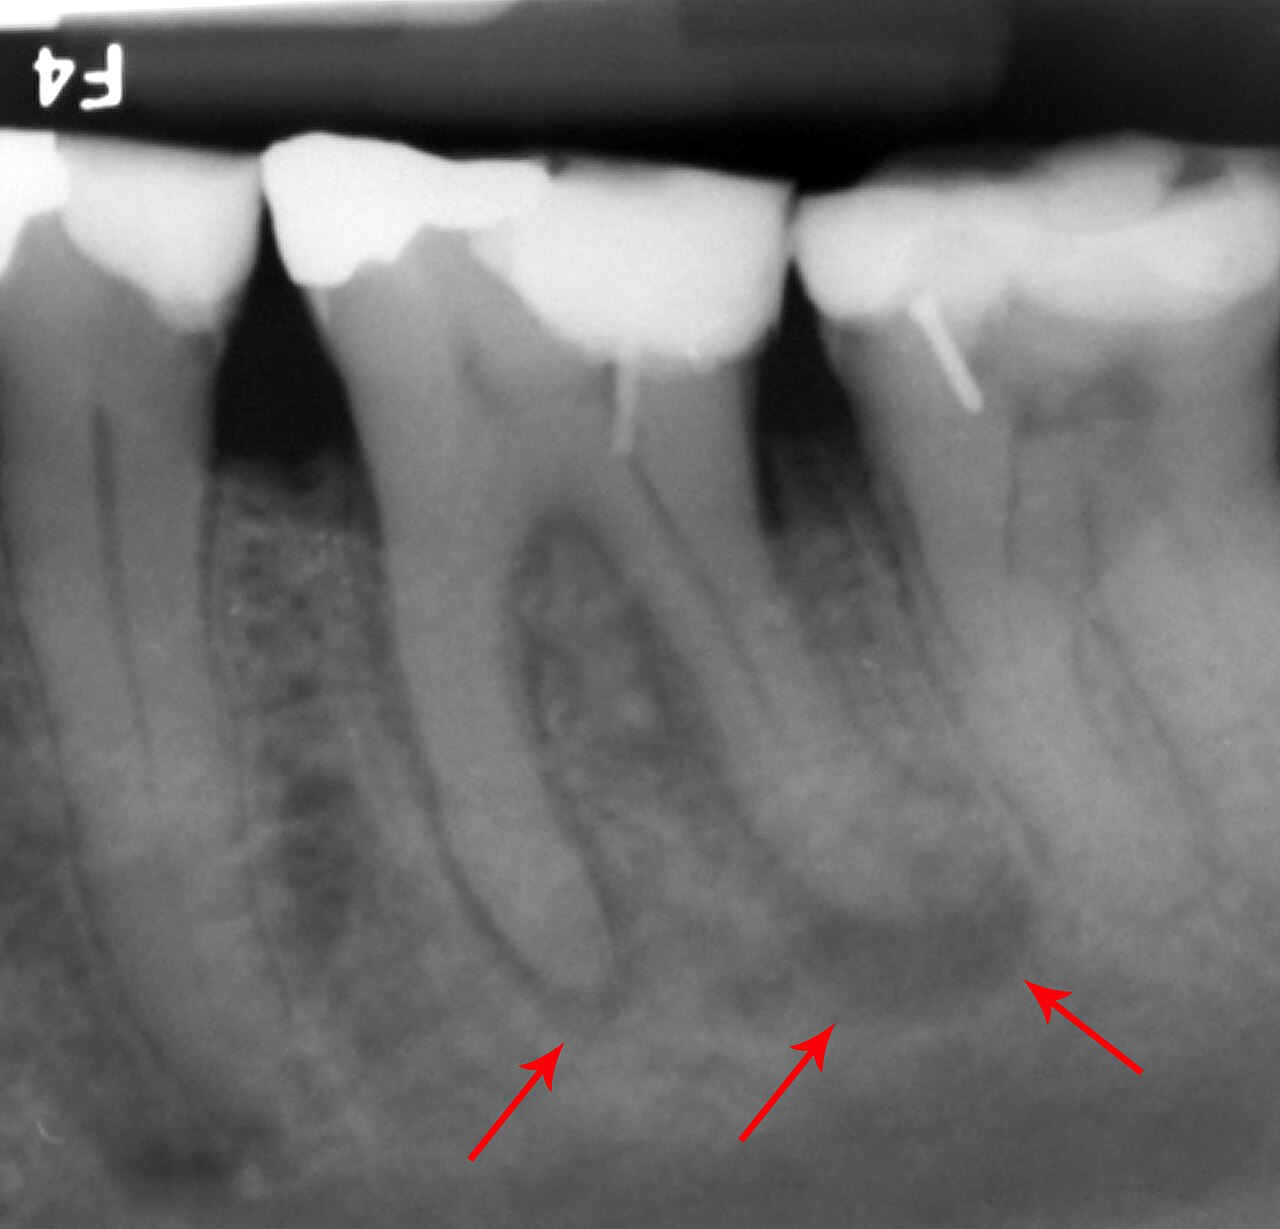

Periapical radiograph phantom showing 2-3 teeth with roots, periodontal ligament, alveolar bone, and surrounding...

Dental phantom showing common pathology: carious lesions, periapical abscess, root resorption, and a metallic restoration